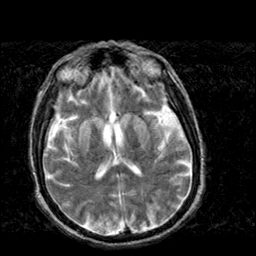

Creutzfeld-Jakob disease: T2-weighted MR -- Slice #13

[Home][Help][Clinical] Slice 13